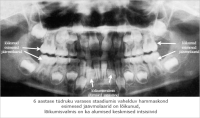

Suutervis

koolis